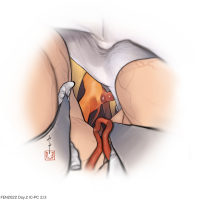

FEN2022シリーズ